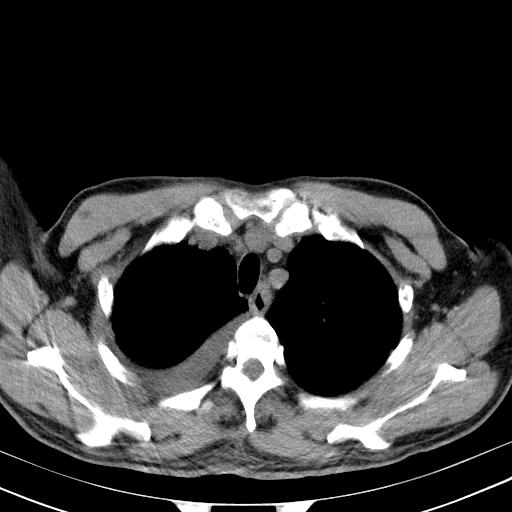

以下是引用zjzjr在2010-3-21 17:39:00的发言:[br]右下中心型肺癌并阻塞性肺炎/不张,纵膈淋巴结肿大,右侧大量胸腔积液,左侧少量胸腔积液

以下是引用zxl51642在2010-3-21 17:06:00的发言:[br]右下中心型肺癌并阻塞性肺炎/不张,纵膈淋巴结肿大,右侧大量胸腔积液,左侧少量胸腔积液,少量腹水。建议纤维支气管镜进一步检查。